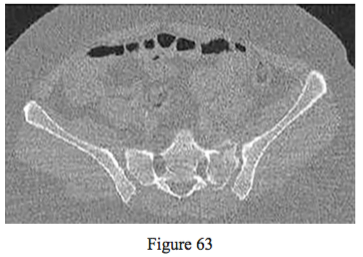

Figure 63

Figure 63 is the CT scan of a 43-year-old woman who was involved in a motor vehicle collision and sustained multiple injuries including a pelvic fracture. The injury shown in the CT scan is most consistent with a (an)

combined-mechanism (CM) injury with a VS mechanism with a completely unstable right hemipelvis and a LC injury resulting in a completely unstable left hemipelvis.

anteroposterior compression (APC) mechanism resulting in a completely unstable right hemipelvis.

APC mechanism resulting in a partially unstable right and left hemipelvis.

vertical shear mechanism resulting in a partially unstable left hemipelvis internal rotation and

a completely unstable right hemipelvis external rotation (open book).

lateral compression mechanism type 3 resulting in a partially unstable left hemipelvis internal

rotation and a partially unstable right hemipelvis external rotation (open book).

PREFERRED RESPONSE: 5